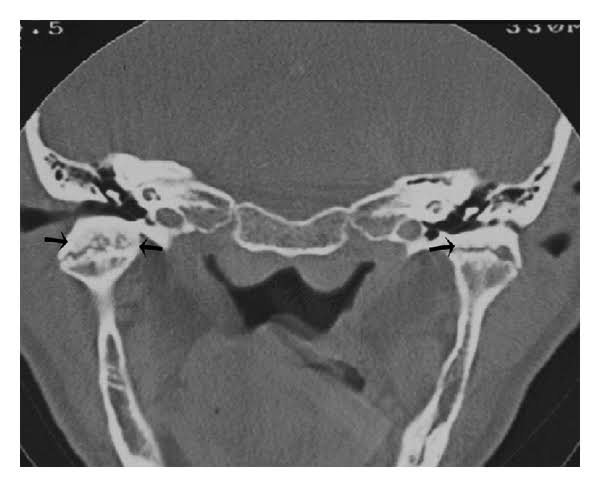

Image :- Google